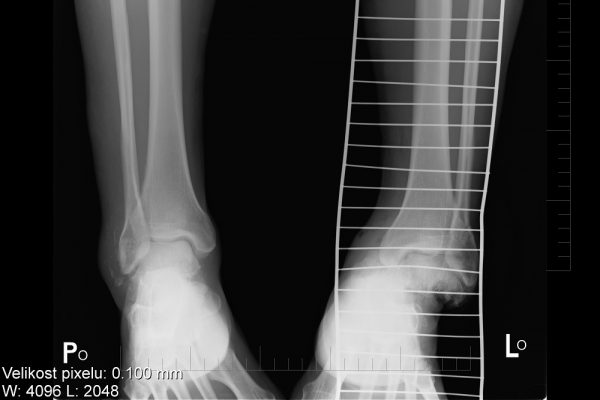

Moje kotníky po pádu ve Vysokých Tatrách

Moje nožičky_004